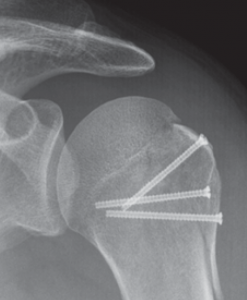

Hierbei werden unterschiedliche Implantate zur Stabilisierung des Knochenbruches in Abhängigkeit vom Frakturtyp verwendet. So können Frakturen entweder mittels Drähten, Schrauben, Platten oder Marknägeln stabilisiert werden.

Vielfach lassen sich teilweise auch komplexe Oberarmkopffrakturen minimal-invasiv versorgen. Dabei gelingt es über kleine Hautschnitte die verschobenen Fragmente wieder aufzurichten und mittels Humerusblock sowie zusätzlichen Schrauben die Fraktur zu stabilisieren (Abb. 53 bis 55). Neben der gewebeschonenden Versorgung stellt auch das günstige kosmetische Ergebnis einen entsprechenden Vorteil dar.